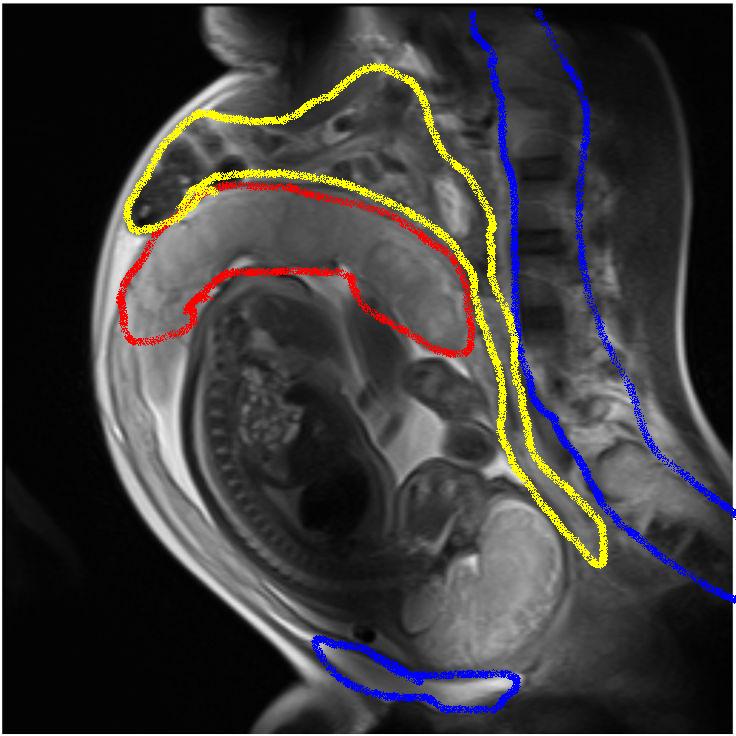

@avidkeo, that is so cool, but where are mom's organs? I realized they were scrunched, but not THAT scrunched!

If you like I can try to highlight things for you?

OK I'm bored so I did a highlighted version - please remember I don't work in MRI so I am not an expert.

The red is the placenta, the blue is the bones (pubic symphysis and spine, and the yellow is the intestines. ETA I think the scan was taken in a way to get the spine of the baby going by how it is aligned.

Yup, that's why you feel full after only a few mouthfuls! Because this image is through the middle of the patient (think a vertical slice through your nose, breastbone and between your legs) you cant see the other organs. Your stomach would show squashed as well.

@avidkeo can you label whats what on that mri? like what part is the stomach, intestines etc... i just can't see them all!

I think because the image is of baby, and not mum, it is taken in an unusual angle. I don't see the stomach here, but can see a little bit of the liver (the dark area just above the top yellow line).

Its difficult to explain but to me it looks like this "slice" was taken off centre - slightly to the right, and on a bit of an angle, therefore the stomach doesn't show up. What you can see is small and large intestine squashed together. Sorry I can't be more help!!